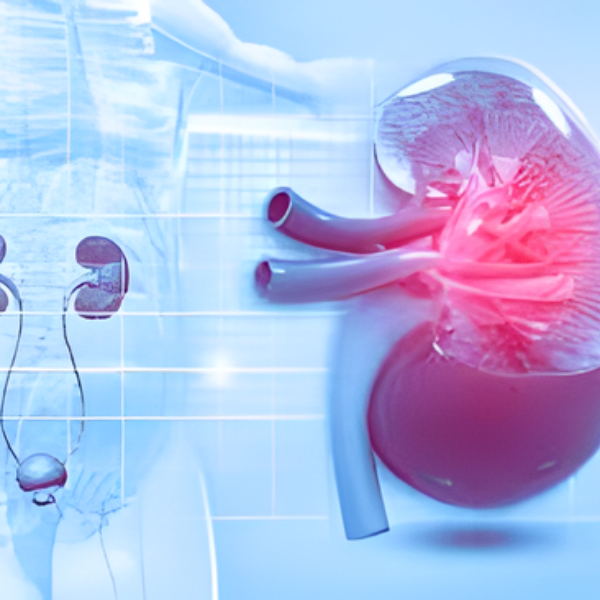

Kidney Stones

02. Stone removal and urinary tract management.

Effective treatment for kidney and urinary stones along with complete care for infections, obstructions, and bladder disorders.